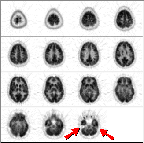

The first step in analyzing image quality is to look for artifacts. For example, this scan is too noisy.

This scan is too smooth.

This scan is just right! (with apologies to the author of "Goldilocks and The Three Bears")